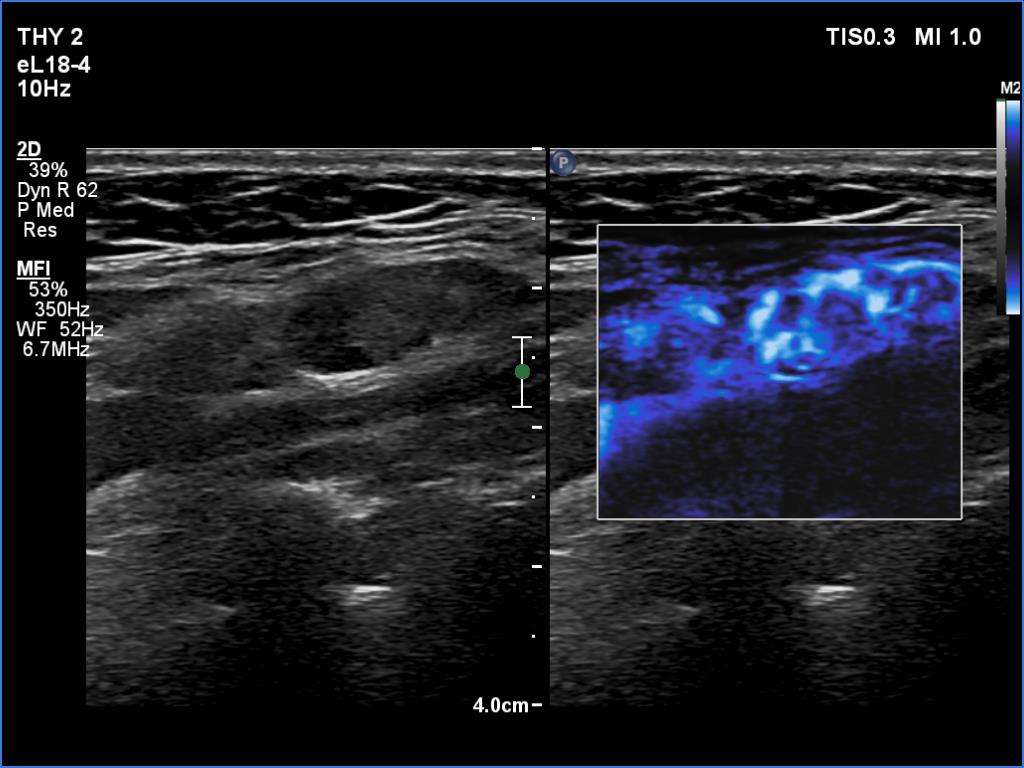

18 months after surgery (ultrasonographic picture 9)

Left side of the neck, longitudinal scan, microflow imaging. There are vessels running both at the periphery and in the central part of the lymph node.